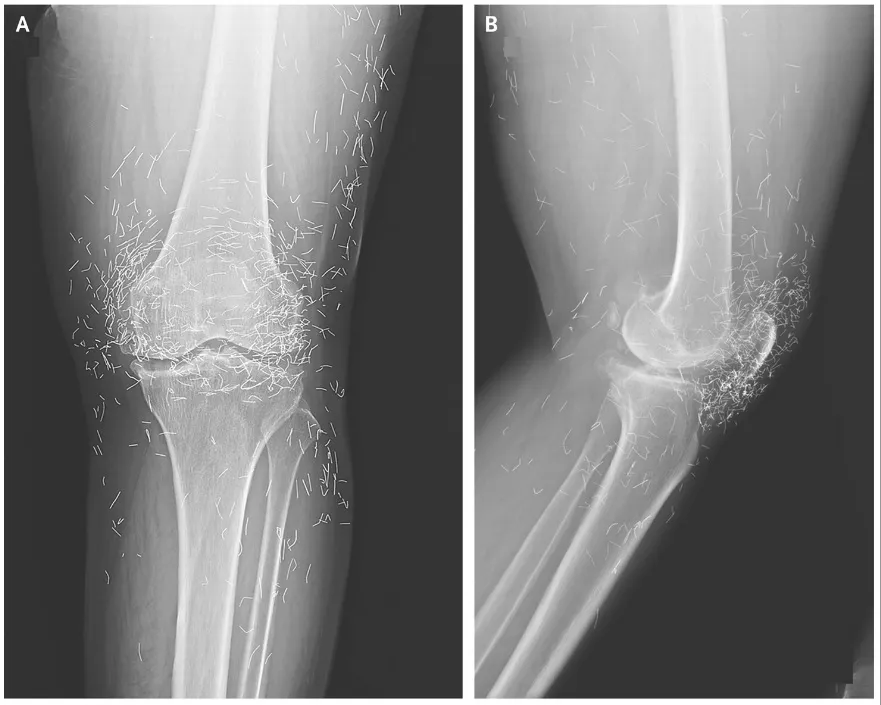

Διαγνωστικό δίλημμα: Ο έντονος πόνος στο γόνατο μιας γυναίκας αποκάλυψε... «χρυσές κλωστές» στις αρθρώσεις της